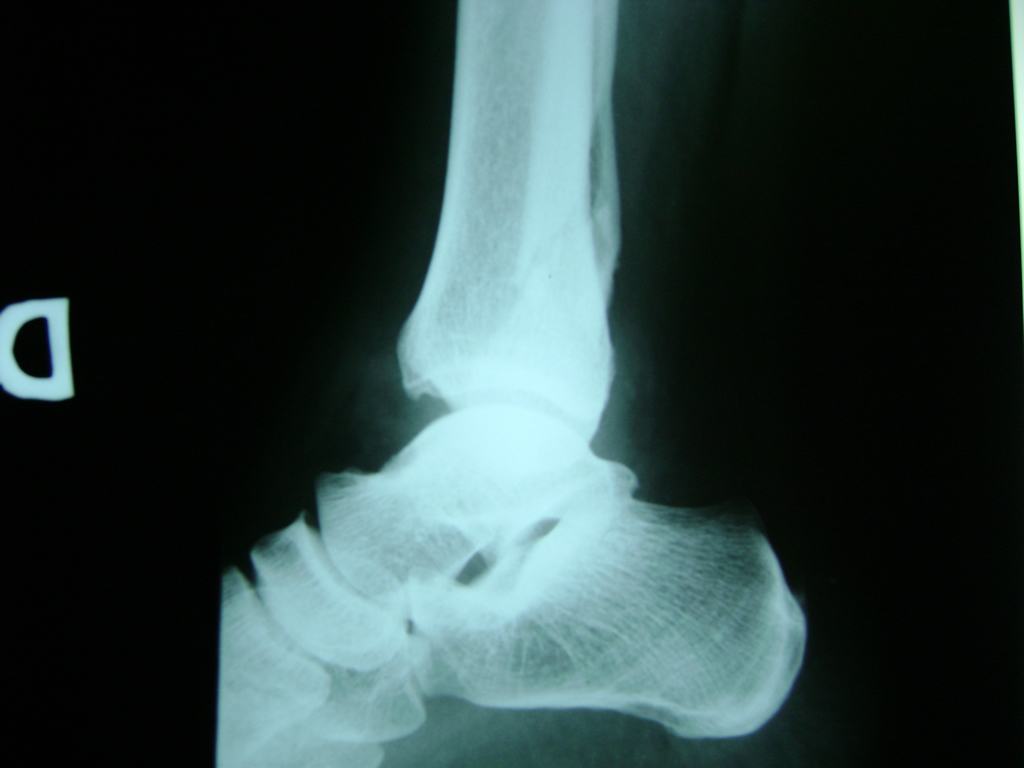

Una fractura de tobillo es la rotura de uno o más de los huesos del tobillo. Estas fracturas pueden ser:

Algunas fracturas de tobillo pueden requerir cirugía si:

- Los extremos de los huesos están desalineados entre sí (desplazados).

- La fractura se extiende hasta la articulación del tobillo (fractura intra-articular).